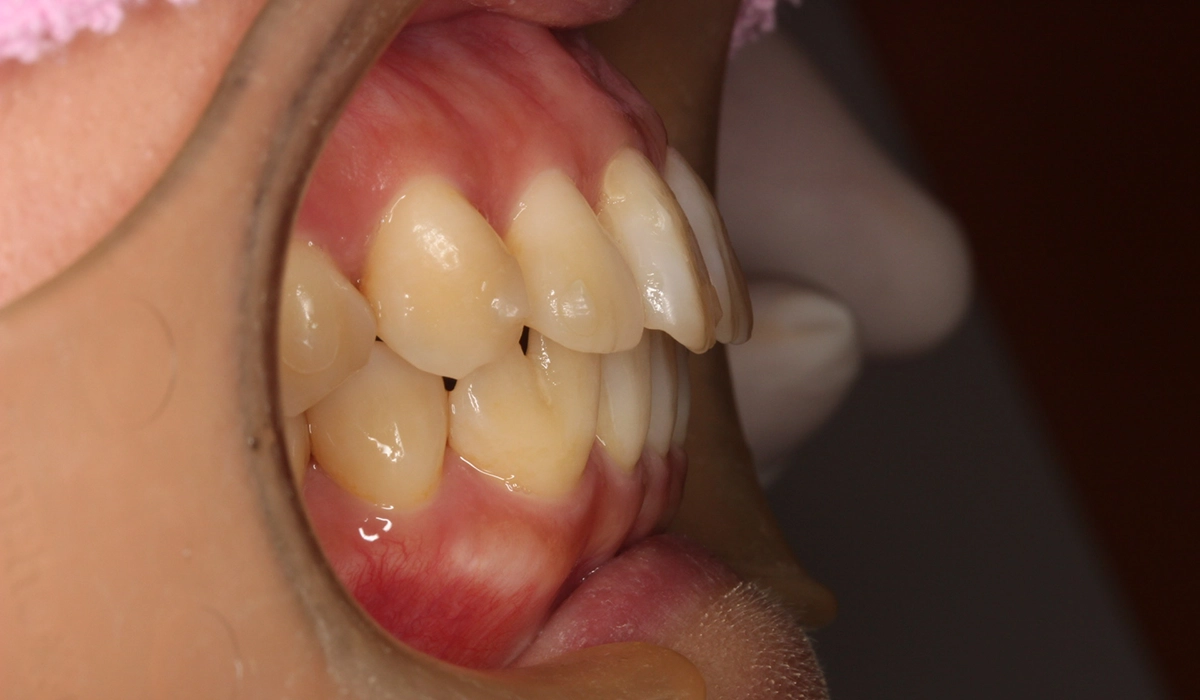

術前:オーバージェット

術後:オーバージェット